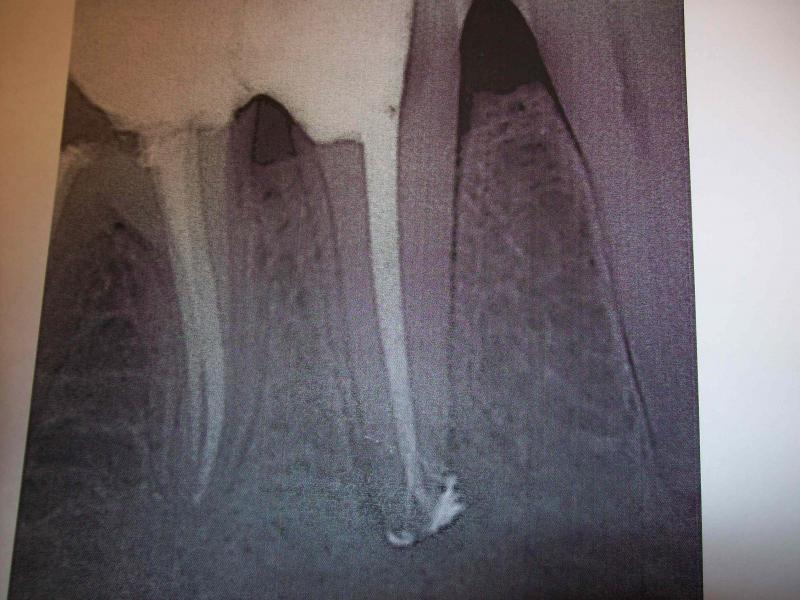

DR JET LOVES ROOT CANALS

General Dentist, Performs Root Canals ONLY - Microscope Trained Dentist

"DR. JET'S MISSION IS TO PERFORM ROOT CANALS FOR A REDUCED FEE USING THE LATEST TECHNOLOGY AND TECHNIQUES TO SERVICE THE MANY PEOPLE WHO ARE UNINSURED OR UNDER-INSURED GIVING EVERYONE AN OPPORTUNITY TO SAVE THEIR TOOTH!"

**PLEASE BE AWARE THAT A ROOT CANAL IS AN ATTEMPT TO SAVE YOUR ALREADY DAMAGED TOOTH. THERE IS NO GUARANTEE THAT ANY TOOTH CAN BE SAVED BUT DR JET WILL DO HIS BEST TO HELP YOU. THE OTHER OPTION IS TO EXTRACT YOUR TOOTH